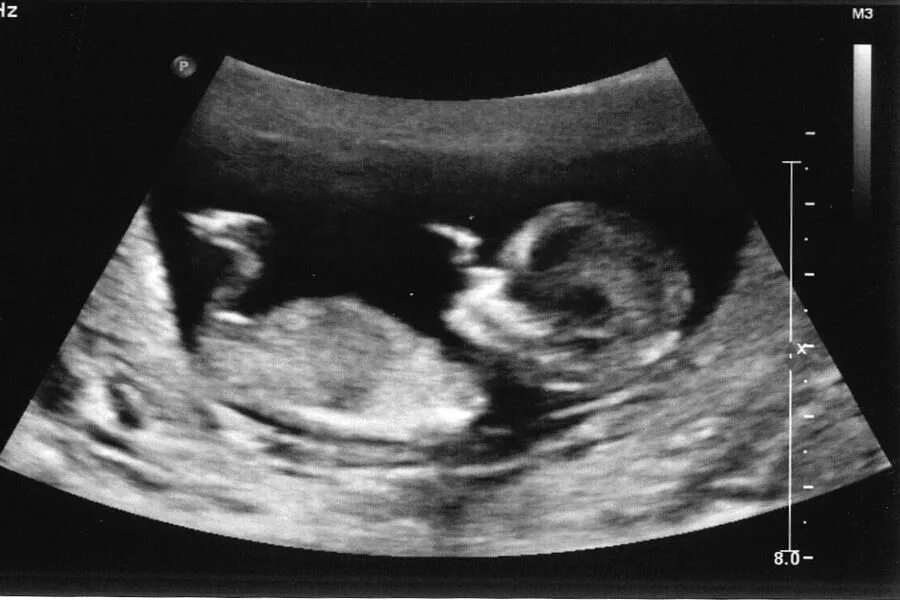

Ребенок в 13 недель